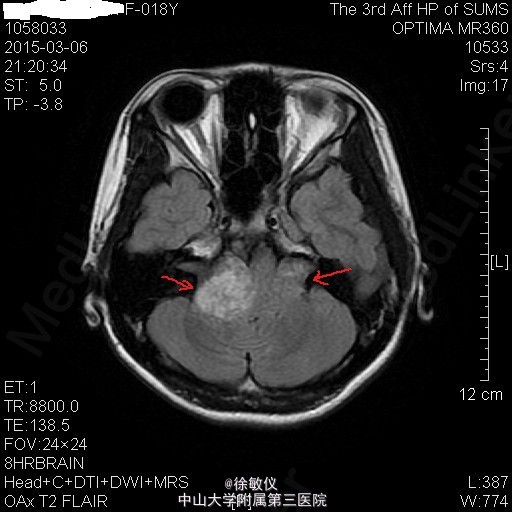

青年女性,主诉:左侧面部麻木,右侧听力下降半年。

查体:神清,查体合作,对答切题。颈软,无抵抗。左侧面部浅感觉痛觉过敏。双侧眼球运动正常,双侧视野粗测无缺损。右侧听力粗测听力下降。双侧瞳孔等大等圆,直径3mm,对光反射灵敏。双侧肢体肌力5级,肌张力正常。病理征未引出。 辅查:头颅MR提示:双侧桥小脑角区、鞍上池右侧、左侧三叉神经颅内段及枕部多发占位,考虑为神经纤维瘤病II型。

诊断:双侧听神经鞘瘤 排除手术禁忌症后,在全麻下行显微镜下经右侧乙状窦后入路右侧桥小脑角区占位病变切除术,术程顺利。术后于SICU监护治疗1天后顺利转回我科,予抗感染、脱水降颅压、营养支持及对症治疗,患者恢复良好。 术后病理诊断:(桥小脑角占位)形态结合免疫组化结果,符合神经鞘瘤。免疫组化结果(⑥):S100(+),Vim(+),Ki-67(1%+)。 术后复查头颅MR示:1、右侧听神经瘤术后改变,右侧桥小脑角区占位大部分已切除,术区少量积液同前;左侧侧脑室内少量积血,基本同前。 2、左侧桥小脑角区、鞍上池右侧、左侧三叉神经颅内段及枕部多发占位同前,考虑神经纤维瘤病。